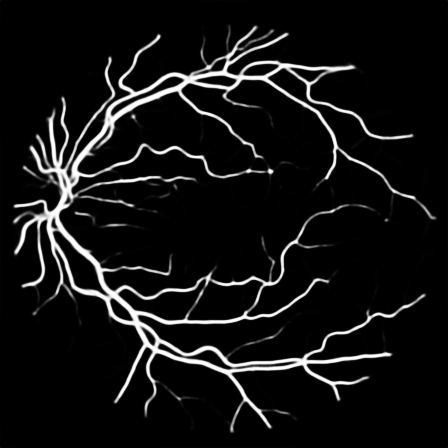

To justify the performance of our model, we compare the 4 metrics with 8 representative previous works from all 3 open-access datasets. The comparison results presented in Table 1 show that our MP-Net model outperforms the state-of-the-art methods regarding accuracy and in all three datasets, which meter the practical prediction quality and the overall prediction quality independent on thresholding specifications. The advancement is greater in the DRIVE dataset. It’s related to the fact that the DRIVE dataset contains more thin vessels, which is the main target of our model. Specificity is also the highest in DRIVE and CHASE_DB1 while sensitivity is highest in STARE. Particularly, our method outperforms ML-UNet [2] and JL-UNet [4] which adopt a different multi-class approach to also especially tackle the thin-vessels challenge. Figure 2 shows an example of our segmentation maps on DRIVE. As can be seen, most thin vessels and boundary areas have been meticulously picked up.